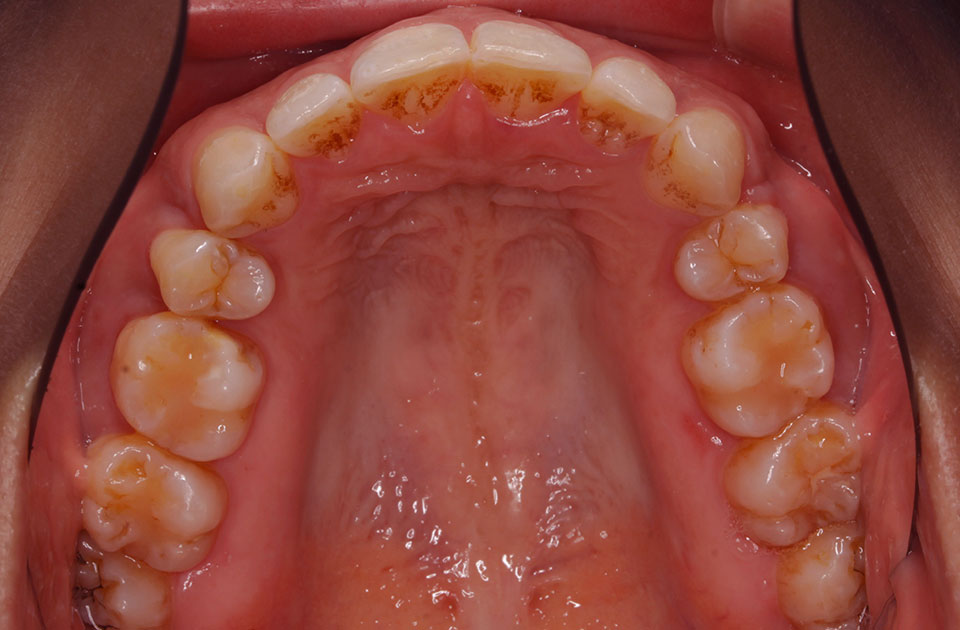

矯正前 上顎